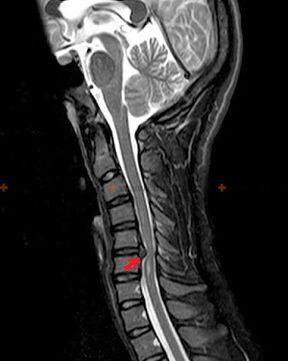

Diagnostika in rentgenski znaki

Osteohondroza je rentgenska diagnoza, saj je podrobna klinična slika na voljo le v trenutku poslabšanja, medtem ko se lahko spremembe v hrbtenici pojavijo ob popolnem subjektivnem dobrem počutju osebe. Brez rentgenskega pregleda lahko govorimo samo o domnevni osteohondrozi, saj lahko podobne simptome povzročijo druge bolezni (miozitis, vretenčne neoplazme in druge).

Za diagnosticiranje osteohondroze se uporabljajo naslednje raziskovalne metode: radiografija (po možnosti s funkcionalnimi testi), MSCT in MRI. Slednja študija je najprimernejša zaradi dejstva, da omogoča zelo jasno vizualizacijo stanja medvretenčnih struktur.

Rentgenski znaki osteohondroze vključujejo naslednje spremembe hrbtenice:

- Zmanjšana višina medvretenčnih ploščic.

- Prisotnost robnih kostnih izrastkov.

- Kršitev lokacije vretenc relativno drug proti drugemu.

- Deformacije teles in lokov vretenc itd.

Prisotnost zgoraj opisanih sprememb, pa tudi spremembe v strukturi medvretenčne ploščice, odkrite z MSCT in MRI, so zanesljivi znaki, ki potrjujejo prisotnost osteohondroze.